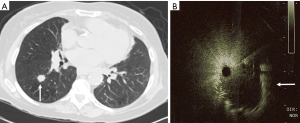

The CP-EBUS allows for real-time ultrasound guided tissues sampling. The CP-EBUS incorporates a convex transducer at the tip of a flexible bronchoscope to provide an ultrasound image that is parallel to the insertion direction of the bronchoscope (18). Some incorporate a saline filled balloon on the tip to improve approximation with the airway, while others utilize direct contact by the probe. A Doppler mode allows for assessment of vasculature and an instrument channel permits biopsy under direct visualization (Figure 2).